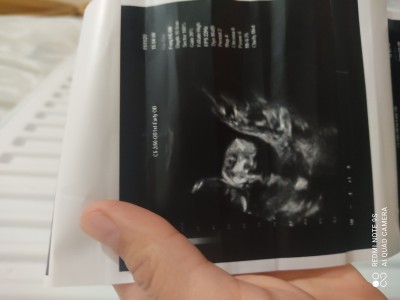

Cinsiyetimiz resimli

23 haftalık gebelik

Sanki kız bebeğin canım

Gördüğüm iki bacaksa orta kısim boş duruyor canım kız bence çok net değil ama

Canım banada 15 haftalıkken kız dedi ama 19 da gittiğimde erkek dedi bacak arası doluydu seninki bet bir şekilde boş görünüyor cinsiyet yanilmasi olucagini düşünmüyorum haftan büyük çünkü